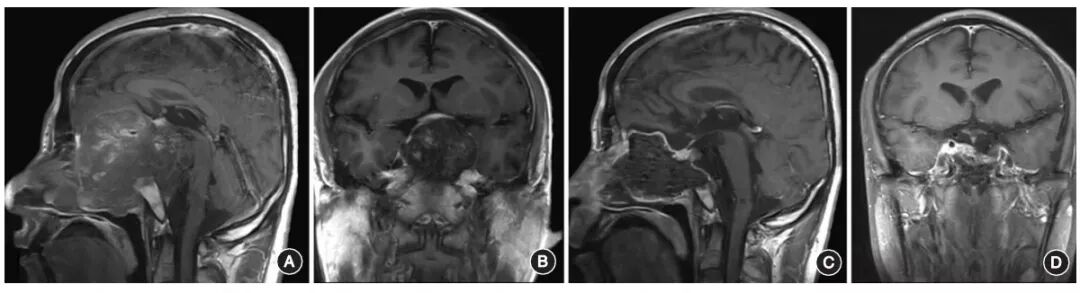

肿瘤两侧为颈内动脉区域,在该区域操作时,应动态使用多普勒超声明确颈内动脉的位置和走行,以避免术中损伤。对于复发颅底硬膜外脊索瘤,肿瘤切除后,尽量保留残存硬膜,以减少术后并发症的发生(图1)。对于已经侵入硬脑膜内的肿瘤或本身就是硬膜内的脊索瘤,肿瘤切除后可清晰显示后方的脑干、基底动脉、视神经等肿瘤背侧结构,此时的颅底缺损应尽量使用带血管蒂的黏膜组织进行重建(图2)。

图1:复发巨大全斜坡脊髓瘤,肿瘤未侵入硬脑膜内A,B.术前头颅MRI增强扫描显示肿瘤全部切除